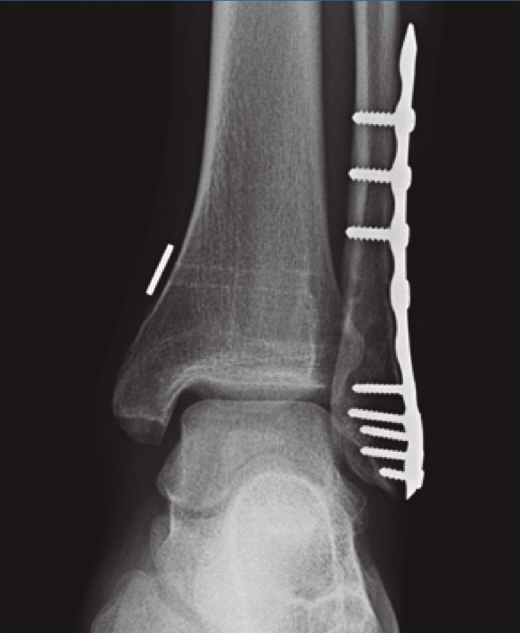

Una vez conseguida la reducción de la sindesmosis, debemos proceder a su estabilización y, en este sentido, pocos temas han despertado tanta controversia en la literatura reciente como el sistema ideal que mantenga en el tiempo de forma satisfactoria la reducción conseguida en el tratamiento inicial(6,7,8). El tornillo de fijación transindesmal o fijación rígida ha sido el método más utilizado y todavía hoy es considerado el patrón oro; sin embargo, en un intento de producir una reducción y fijación más anatómica, se han desarrollado en las últimas 2 décadas las denominadas técnicas de fijación dinámicas(7)(Figura 1).

Figura 1. Fractura del maléolo peroneo sintetizada con placa anatómica y sistema TightRope® a los 2 años de seguimiento con correcta reducción de la mortaja y la sindesmosis.